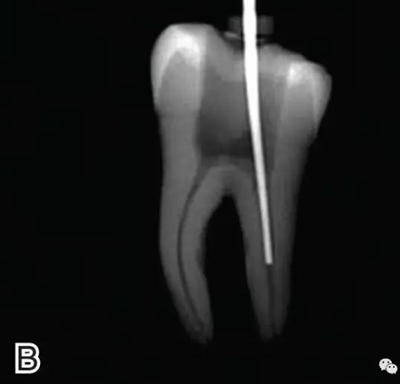

選擇的小號垂直加壓器應(yīng)能自由到達(dá)距根尖4~5 mm(有學(xué)者提出3~4 mm)的位置并能輕微接觸根管壁;中號垂直加壓器應(yīng)能自由到達(dá)距根尖7~8 mm的位置并能輕微接觸根管壁;大號垂直加壓器應(yīng)能自由到達(dá)距根尖10~11 mm的位置并能輕微接觸根管壁。用橡皮片做好標(biāo)記(圖2)。

圖2 選擇垂直加壓器,A.試垂直加壓器 B.垂直加壓器在根內(nèi)的位置